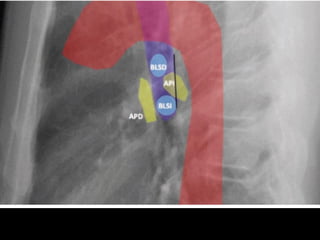

AD: Aurícula derecha AI:Aurícula izquierda VI: Ventrículo izquierdo VA: Válvula aórtica VP: Válvula pulmonar VT: Válvula tricuspídea VM: Válvula mitral AD VD AI VI Tr Mt Ao P Botón aórtico Arteria pulmonar AI VI Art. subclavia Vena cava superior Vena cava inferior Arteria pulmonar derecha ‘interlobar’ AD VA VP VT VM Aorta**